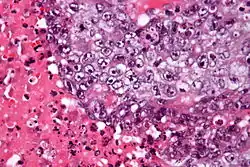

| Micrograph of an embryonal carcinoma showing its typical features – prominent nucleoli, marked nuclear atypia, necrosis, and nuclear overlap. H&E stain. | |

The microscopic features include: indistinct cell borders, mitoses, a variable architecture (tubulopapillary, glandular, solid, embryoid bodies – ball of cells surrounded by empty space on three sides), nuclear overlap, and necrosis.

An important key to distinguish it from other tumors, such as seminoma (vacuolated), teratocarcinoma (three differentiated germ layers), yolk sac tumor (Schiller–Duval bodies), and the Sertoli–Leydig cell tumor (strings of glands), is that the embryonal carcinoma cells are "trying" to evolve into their next stage of development. So in the testicle, they are often observed as blue cells attempting to form primitive tubules.[6]